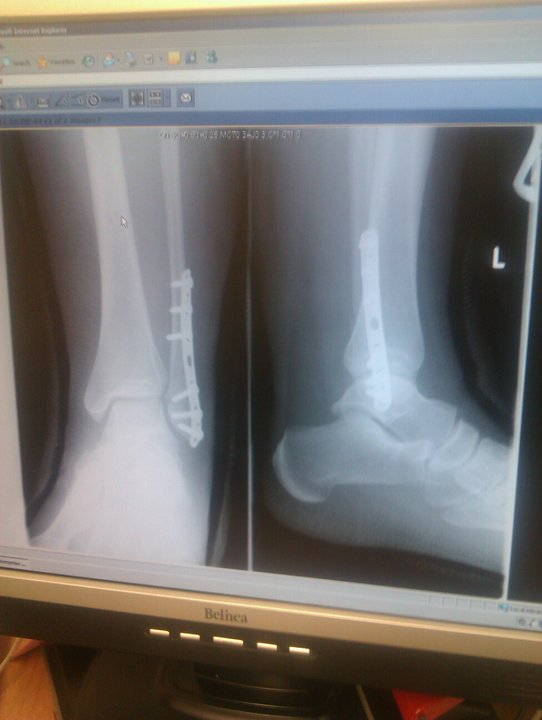

The beginning of my journey started on the 5th December 2011. Yep, right before Christmas and surprisingly not the new year ;). What sparked this change, was that I broke my ankle in July 2011.

My x-ray of the metal plate and six screws in my ankle!

I had been running through our nearby woods as much as I could for the weeks leading up to my injury (which happened on a night out). I was weighed for the first time in a long time before ankle surgery and weighed in at 92KG (203lbs). I had weighed more previous to this, I had once weighed 210lbs but I could never pluck up the courage to see what the scales said.